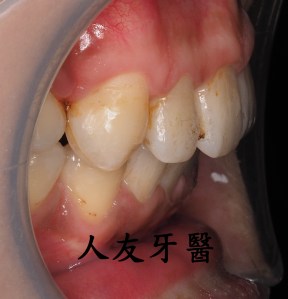

植牙後常見的問題,人工植牙雖然有著不會蛀的金屬質地,但它附屬的地基「齒槽骨」和周圍覆蓋的牙肉跟我們自己的牙齒一樣,植牙周圍若是清潔不乾淨,也會產生牙周病,造成「植體周圍炎」。

但尚未影響到硬組織,被稱為植體周圍黏膜炎;若已破壞到周遭骨頭,被稱為植體周圍炎。若周遭骨被破壞,最後可能造成植體失敗,需要移除,植牙等於做了白工。分析造成植體周圍疾病的原因,主要是細菌,如牙菌斑;咬合力量過大、牙套完成時殘留的黏著劑未清潔乾淨、製作不當的牙套也會。